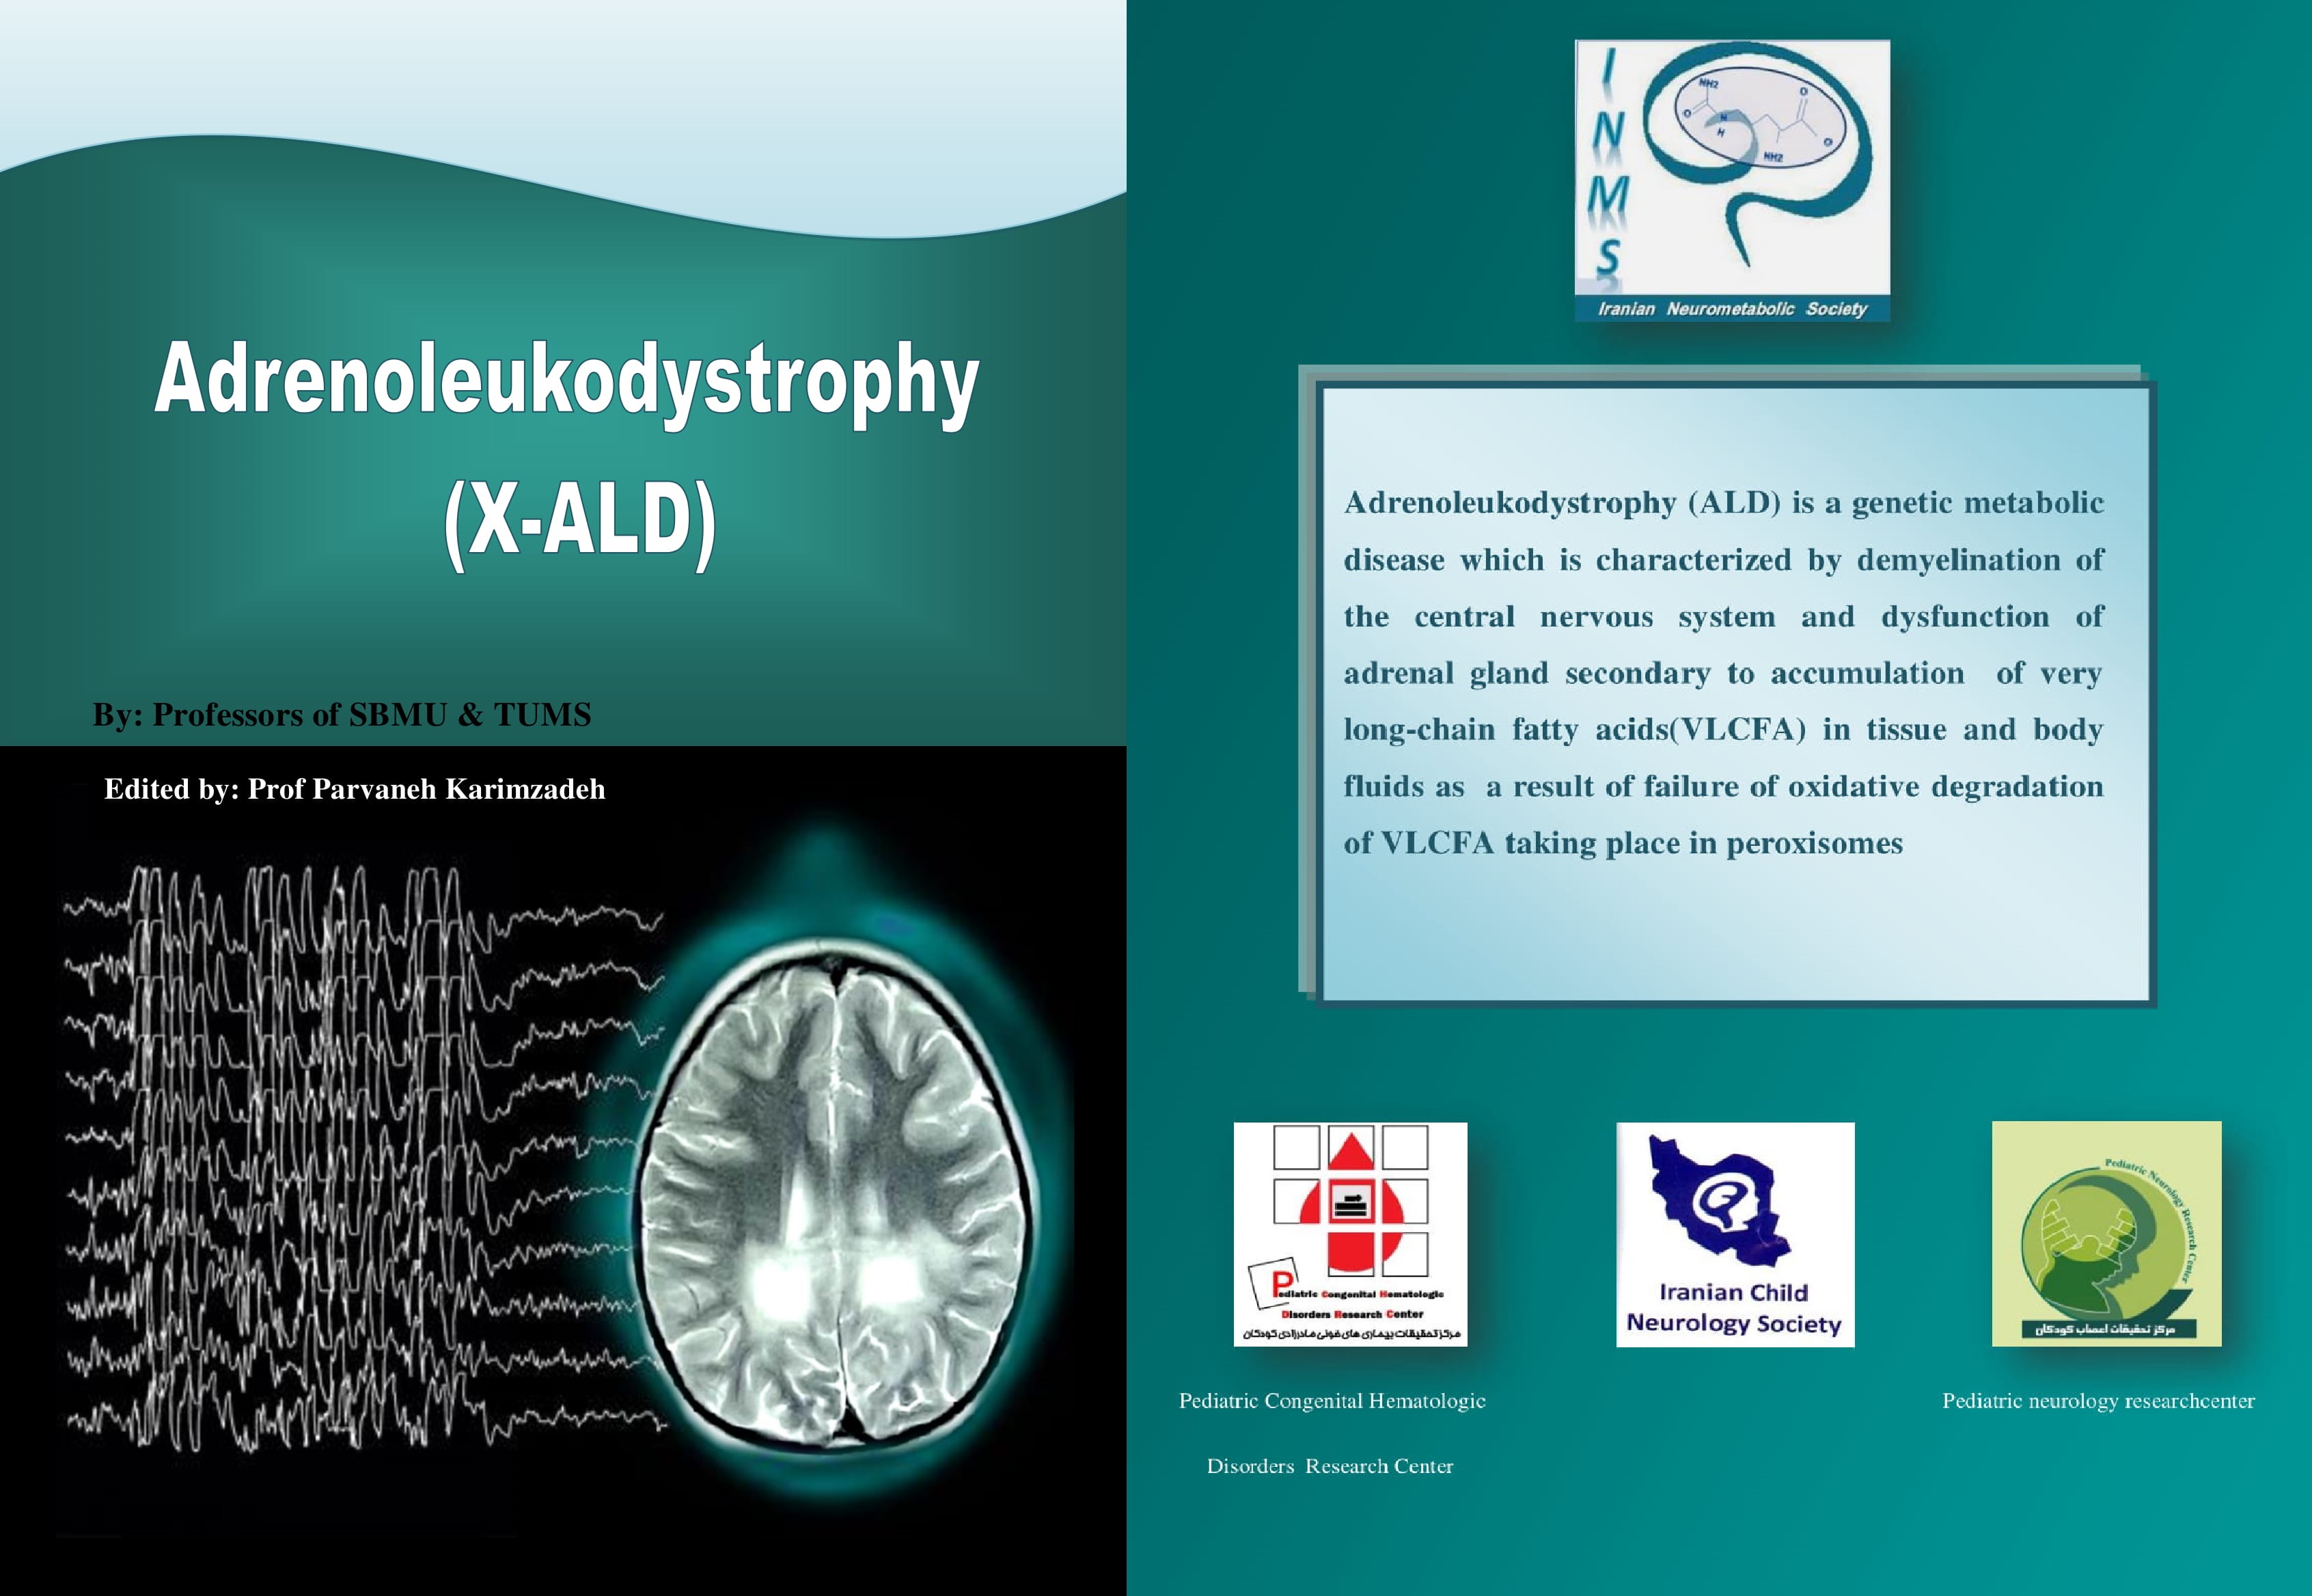

یازدهمین سمینار سالیانه نورومتابولیک ایران(Webinar) عنوان: لکودیستروفی ها